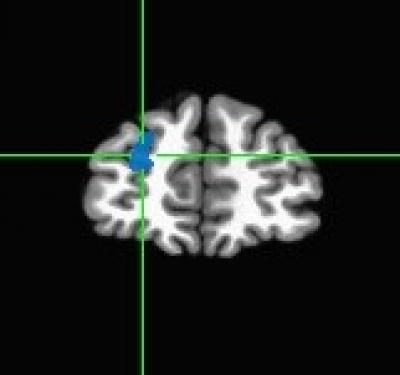

Left Superior Frontal Region

image: Researchers from the Miriam Hospital found that when individuals who have lost significant amounts of weight, and kept the weight off for several years, were shown pictures of food, they were more likely to engage the areas of the brain associated with behavioral control and visual attention, compared to obese and normal weight participants. Specifically, strong signals were observed in the left superior frontal region (pictured) and right middle temporal region of the brain. view more

Those in the successful weight loss maintenance group responded differently to these pictures compared to the other groups. Specifically, researchers observed strong signals in the left superior frontal region and right middle temporal region of the brain – a pattern consistent with greater inhibitory control in response to food images and greater visual attention to food cues.